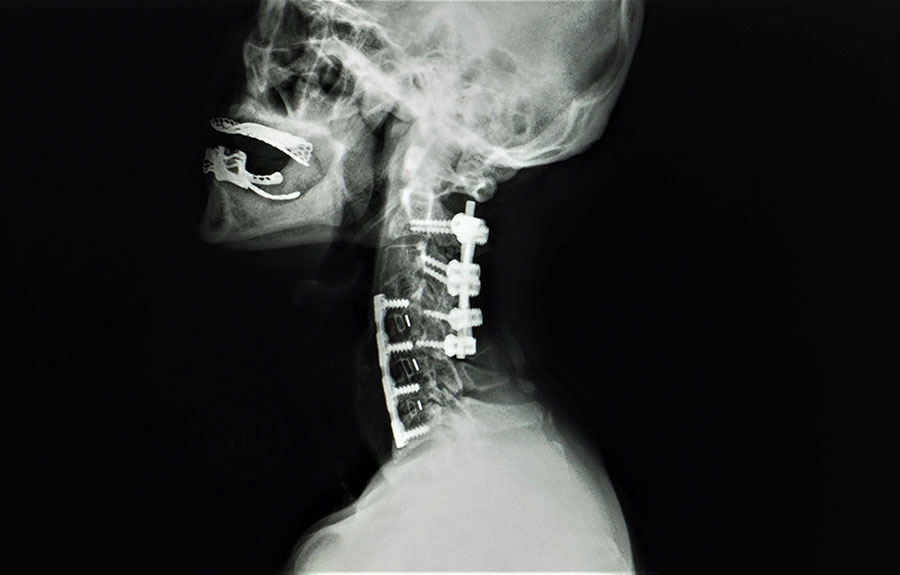

Διάγνωση

Η διάγνωση του κατάγματος βασίζεται σε λήψη του ιατρικού ιστορικού, ώστε να καταγραφούν προηγούμενοι τραυματισμοί και η γενική κατάσταση της υγείας, καθώς και σε κλινική εξέταση και απεικονιστικές μεθόδους. Οι γιατροί αξιολογούν την ένταση του πόνου, την κινητικότητα και πιθανά νευρολογικά ελλείμματα. Η ακτινογραφία είναι συνήθως η πρώτη εξέταση, ενώ η αξονική ή μαγνητική τομογραφία παρέχει λεπτομερή εικόνα της βλάβης, επιτρέποντας την εκτίμηση της συμπίεσης του νωτιαίου μυελού ή των νευρικών δομών.

Η διαδικασία της διάγνωσης περιλαμβάνει, επίσης, αξιολόγηση της σταθερότητας του σπονδύλου και πιθανών μικροκαταγμάτων που δεν φαίνονται σε αρχικές ακτινογραφίες. Σε ορισμένες περιπτώσεις, η χρήση τρισδιάστατων ανασυνθέσεων αξονικής ή ειδικών πρωτοκόλλων μαγνητικής τομογραφίας βοηθά στην ακριβέστερη εκτίμηση της βλάβης στους σπονδύλους και στις γύρω μαλακές δομές, όπως οι μεσοσπονδύλιοι δίσκοι και οι σύνδεσμοι, ενώ διευκολύνει τον σχεδιασμό της θεραπείας.

Η σύγχρονη επεμβατική αντιμετώπιση των καταγμάτων της σπονδυλικής στήλης εξαρτάται από τη σοβαρότητα και τη φύση του κατάγματος. Σε απλά περιστατικά, όπου δεν υπάρχει πίεση στις νευρικές δομές, εφαρμόζεται κυφοπλαστική ή σπονδυλοπλαστική, διαδικασίες που αποκαθιστούν τη μορφολογία του σπονδύλου και μειώνουν τον πόνο. Σε πιο σύνθετες περιπτώσεις, όπου θραύσματα του σπονδύλου πιέζουν τον νωτιαίο μυελό ή τα νεύρα, απαιτείται σπονδυλοδεσία με σκοπό την αποσυμπίεση των νευρικών στοιχείων και τη σταθεροποίηση της σπονδυλικής στήλης.